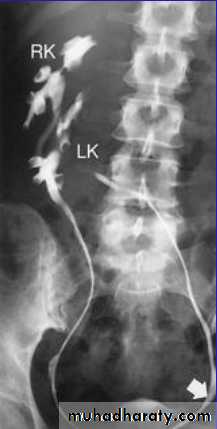

IVU

Normal excretory phase of an IVU (intravenous urogram). This film was taken approximately 10 minutes following IV injection of iodinated contrast material. The kidneys are excreting contrast into non dilated calyces (arrows), renal pelvis (p), ureters (*) and bladder (B).